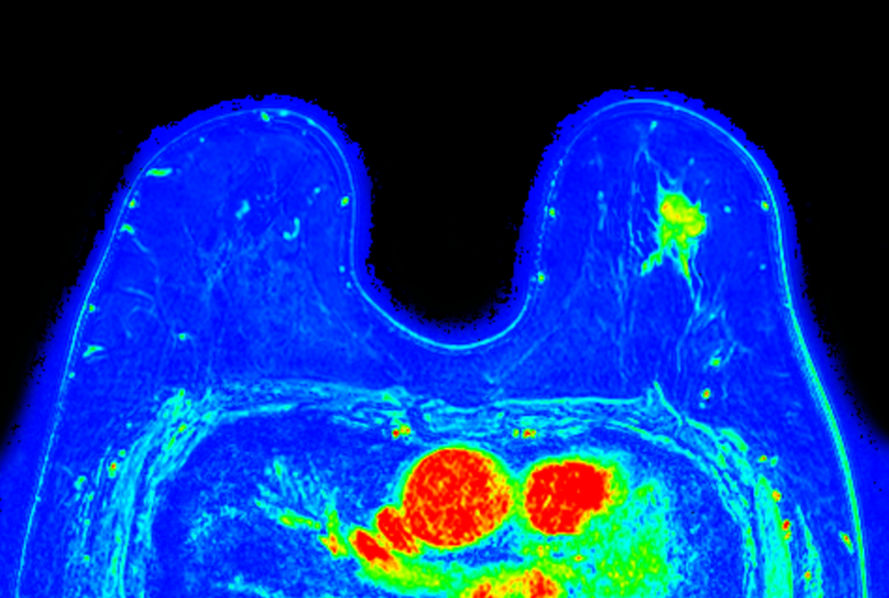

Dynamic 3D mDIXON XD (are under curve) Compressed SENSE